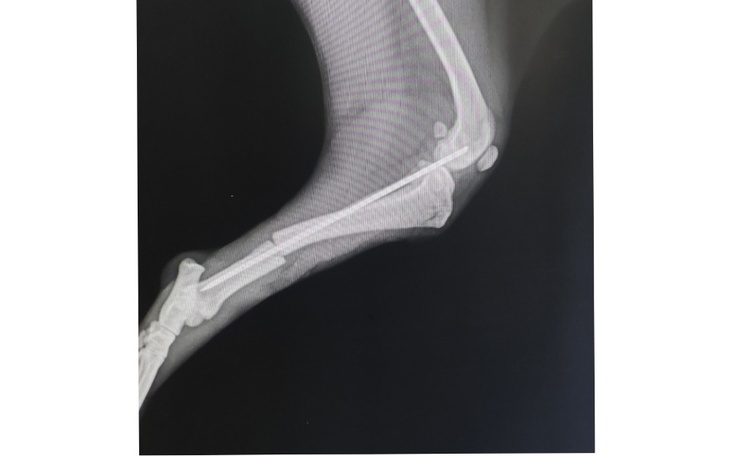

Niespełna roczny szczeniaki z koszmarnym złamaniem łapki 😓 trafił do nas w poniedziałek i pędziliśmy na sygnale do lecznicy. Zdjęcie RTG pokazało złamanie z przemieszczeniem kości.

Dzięki dr Robertowi udało się zoperować Bąbla ( Biszkopta) już we wtorek.